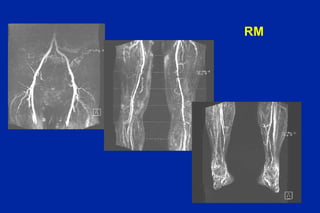

Este documento resume los principales tipos y técnicas de angiografía. Describe brevemente la angiografía, arteriografía, flebografía y linfografía, así como las técnicas de contraste y materiales utilizados. También explica los principales accesos vasculares, la técnica de Seldinger, la angiografía por sustracción digital y algunas técnicas endovasculares comunes.